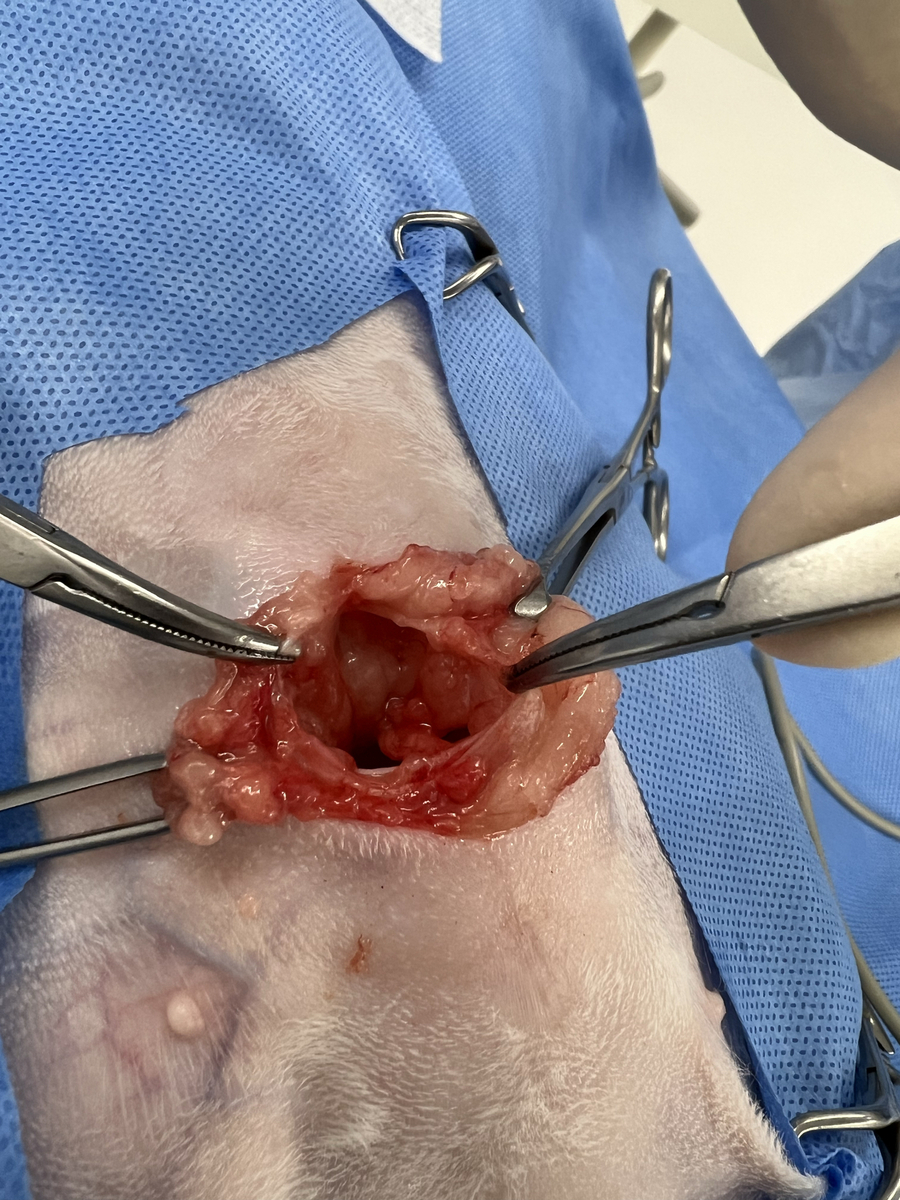

初診の時点では、食欲や元気はあり吐き気や排便障害などの消化器症状はなかったので保護者様と相談の上、手術は見合わせていたのですが、先日お腹の膨らみが徐々に大きくなってきたという事で、空いてしまっているお臍の所と腹壁の穴を閉じる手術を行いました。

開いてしまった所から飛び出ていた脂肪組織などを腹腔内に戻して、腹壁を縫合しました。